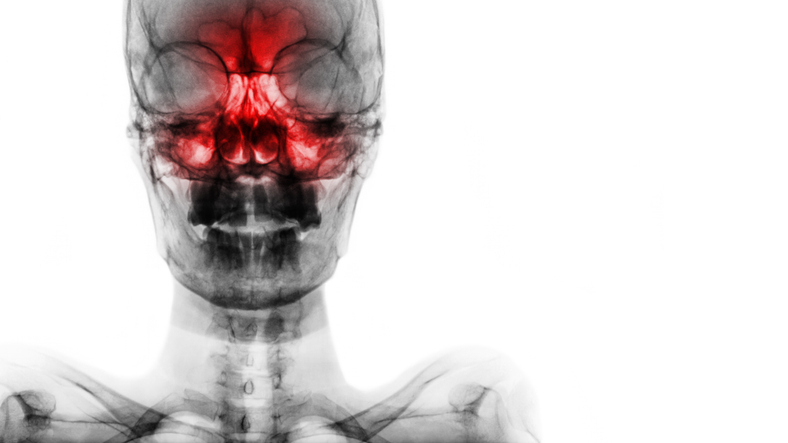

알레르기 비염 환자가 약이 듣지 않으면 막힌 코를 뚫기 위해 수술을 고려해야 한다. 코안 쪽의 조직 하비갑개란 곳이 커져 코막힘을 유발하는데 이 부피를 줄이는 수술이다. 이런 비염 수술을 받으면 효과가 얼마나 지속될지, 합병증은 나타나지 않는지 환자 입장에선 궁금할 수 있다.